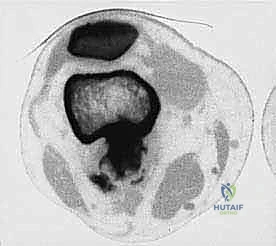

تتميز هذه الأورام بقدرتها على اختراق الأنسجة المجاورة وتكوين ما يُعرف بـ "المنطقة التفاعلية" (Reactive Zone) أو الكبسولة الكاذبة، والتي تحتوي غالباً على خلايا سرطانية مجهرية. هذا المفهوم البيولوجي هو ما يوجه الدكتور محمد هطيف في تحديد مدى الاستئصال الجراحي.

الهدف الأول في جراحة الساركوما ليس فقط إزالة الكتلة المرئية، بل استئصالها مع طبقة من الأنسجة السليمة المحيطة بها لضمان عدم ترك أي خلايا مجهرية. تُصنف الهوامش الجراحية إلى:

- الاستئصال الهامشي (Marginal): الاستئصال عبر الكبسولة الكاذبة للورم. يحمل خطر عودة الورم (Recurrence).

- الاستئصال الواسع (Wide Resection): وهو المعيار الذهبي. يتم استئصال الورم مع طبقة من الأنسجة السليمة المحيطة به (العضلات، العظام). هذا ما يبرع فيه الدكتور هطيف لضمان الشفاء التام.